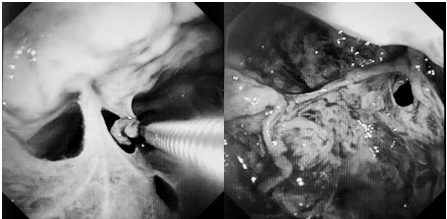

可视化清创:360°探查胸膜腔,精准清除脓苔及坏死组织。

靶向松解:活检钳、电刀分离致密粘连,恢复肺组织活动度。